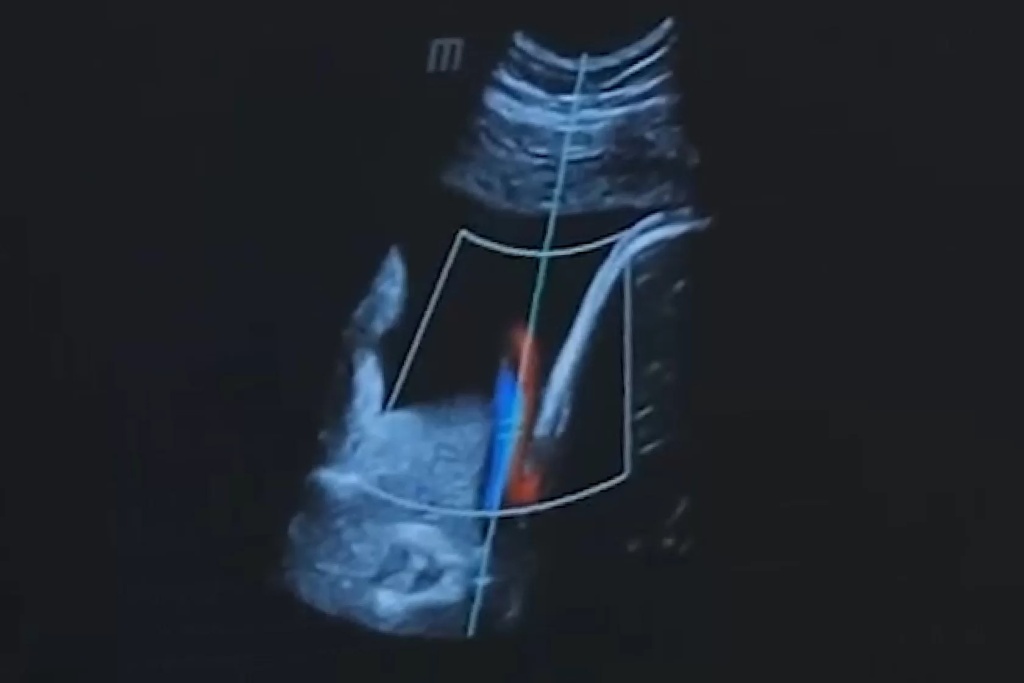

В сфере улучшения акустического доступа при ультразвуковых исследованиях значительные изменения привносят инновационные технологии и разработки. Одной из перспективных областей является применение искусственного интеллекта для анализа ультразвуковых данных. Алгоритмы машинного обучения позволяют автоматически корректировать изображение в реальном времени, оптимизируя акустический доступ даже при наличии сложных анатомических особенностей.

Другим значимым направлением является разработка ультразвуковых трансдьюсеров с многочастотной технологией. Эти устройства обеспечивают более широкий диапазон частот, что улучшает проникновение ультразвуковых волн в ткани и повышает качество изображения.

13.jpg

Примером успешной интеграции новых технологий может служить использование искусственного интеллекта в анестезиологии для точного позиционирования иглы при проведении ультразвукового наведения эпидурального катетера. Это не только сокращает время процедуры, но и уменьшает риск возникновения осложнений.

По статистике, в клиниках, внедривших современные технологии, отмечается улучшение качества ультразвуковых диагностических исследований на 30% и более, что подчеркивает их значимость в повышении эффективности медицинской практики.